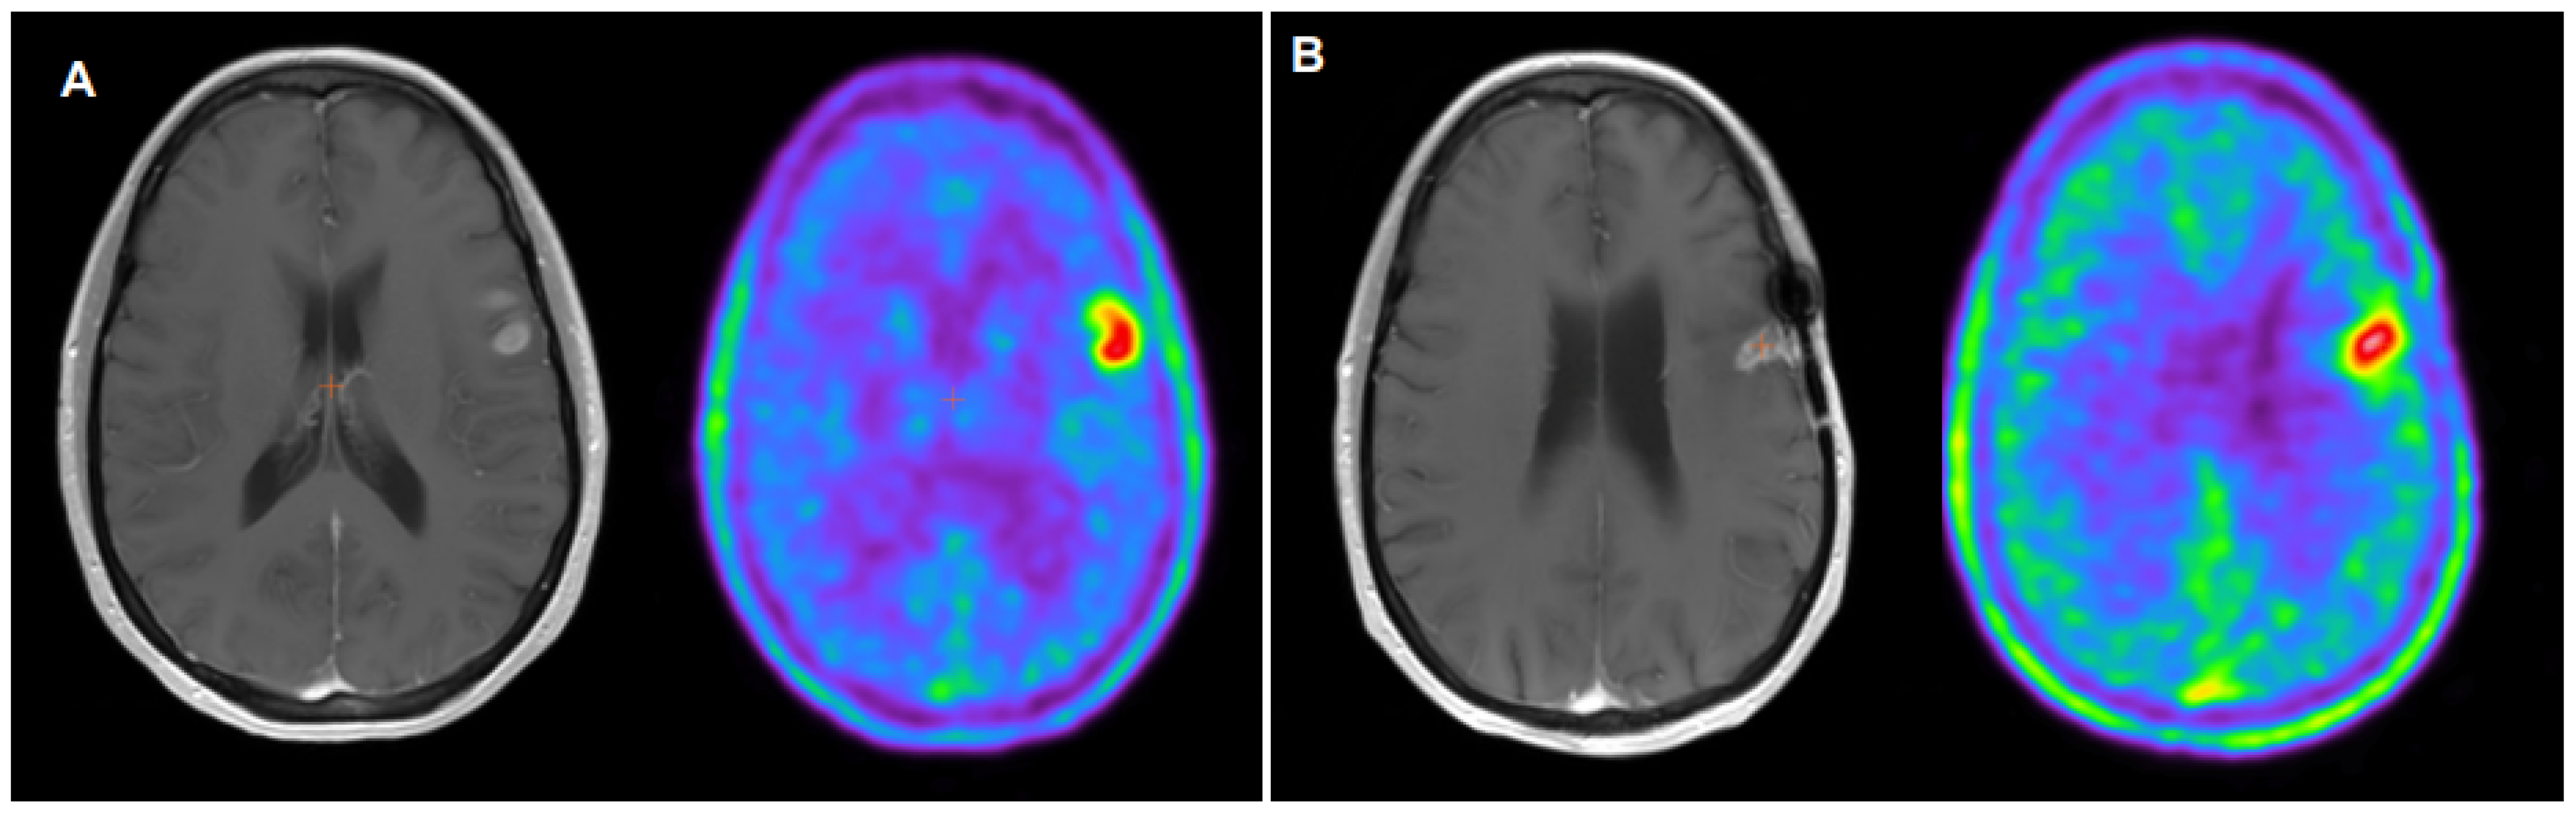

- Galldiks, N.; Dunkl, V.; Stoffels, G.; Hutterer, M.; Rapp, M.; Sabel, M.; Reifenberger, G.; Kebir, S.; Dorn, F.; Blau, T.; et al. Diagnosis of pseudoprogression in patients with glioblastoma using O-(2-[18F]fluoroethyl)-L-tyrosine PET. Eur. J. Nucl. Med. Mol. Imaging 2015, 42, 685–695. [Google Scholar] [CrossRef] [PubMed]

- Kebir, S.; Fimmers, R.; Galldicks, N.; Schäfer, N.; Mack, F.; Schaub, C.; Stuplich, M.; Niessen, M.; Tzaridis, T.; Simon, M.; et al. Late Pseudoprogression in Glioblastoma: Diagnostic Value of Dynamic O-(2-[18F]fluoroethyl)-L-Tyrosine PET. Clin. Cancer Res. 2016, 22, 2190–2196. [Google Scholar] [CrossRef] [PubMed]